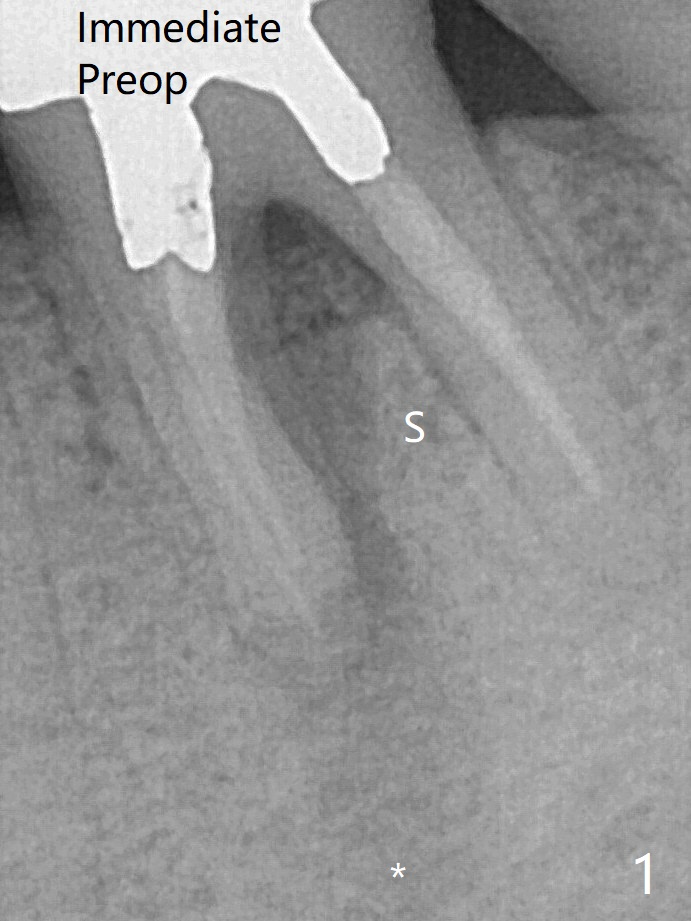

When the patient returns for #15 comp, the bone resorption and swelling at #19 are worse than those 3 years ago (Fig.1,2).  53岁男三年来左下六反复感染(图一,二)。